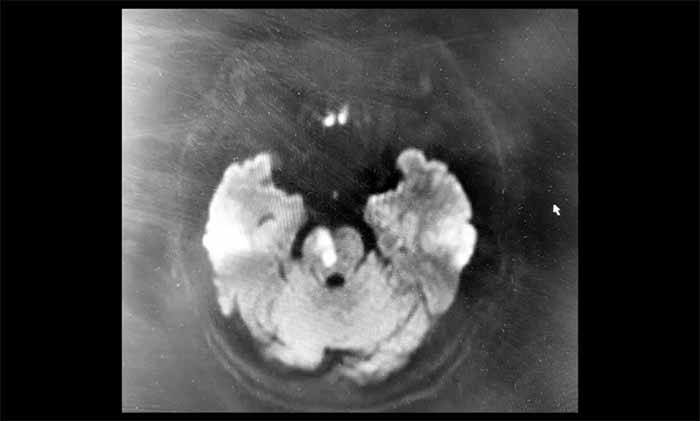

在众多因头晕就诊的患者中,精准识别出后循环缺血,考验着医生的经验与判断力。不久前,潘登博士接诊了一位六旬的女性患者 。她因“头晕、口唇麻木一天”前来就诊,没有出现肢体无力、言语不清等典型中风表现。凭借丰富的临床经验,潘登博士在详细了解病史后,高度怀疑是后循环梗死,立即为她安排了头颅磁共振检查。

磁共振弥散加权成像(DWI)结果显示:脑干区域可见明确的斑片状高信号影,对应的ADC图呈低信号——这是新发脑干梗死的影像证据。脑动脉成像同时提示血管轻度硬化,右侧椎动脉V4段纤细。基于对后循环缺血的深刻认识和对影像细节的敏锐把握,潘登博士结合影像与临床症状,迅速明确了诊断,为患者争取了宝贵的治疗时间。

“这位患者症状看似轻微,但DWI影像显示脑干已发生急性缺血损伤。脑干结构精细、功能关键,即使小范围梗死也可能带来严重后果,或是更重症风险的前兆。”潘登博士说。